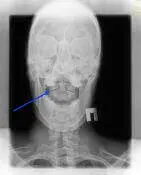

Рентгенографія суглобів голови проводиться через відкритий рот. Добре видно зубовидний відросток і суглоби голови.

При цьому діагностуються:

- тимчасове незрощення верхівки зубовидних відростка з основною його масою;

- вроджена слабкість поперечної і (або) крилоподібні зв’язок атланта;

- асиміляція атланта – часткове або повне його злиття з потиличної кісткою;

- незрощення половин задньої дуги атланта (spina bifida posterior occulta) або незрощення задньої дуги з бічними масами (spondilolisis), відсутність задньої дуги атланта;

- вроджені зміни форми зубовидних відростка (збільшення, зменшення і ін.);